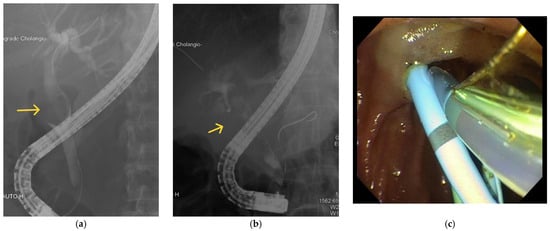

5.4. Endoscopic Retrograde Cholangiopancreatography (ERCP)

5.5. Percutaneous Transhepatic Cholangiography (PTC)